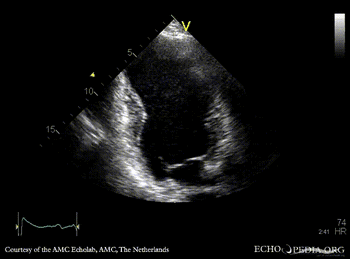

Large aneurysm of LV

PLAX: large aneurysm of left ventricle